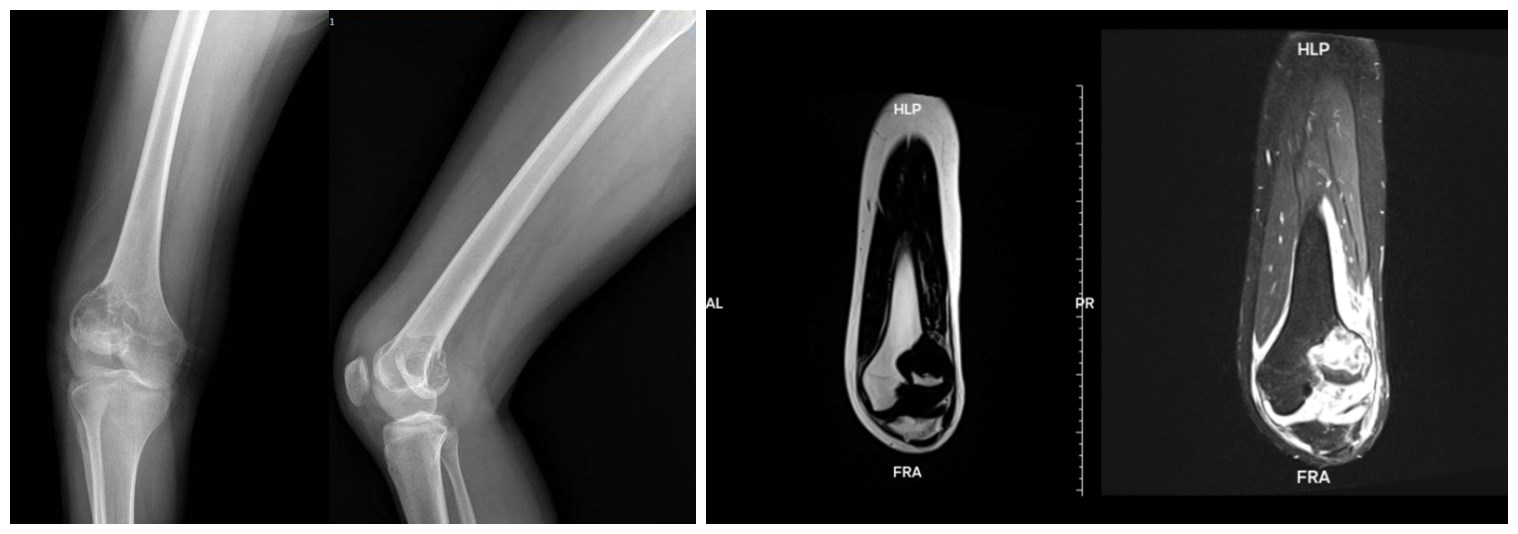

患者李女士(化名)因右膝扭伤后肿胀疼痛、活动受限前来就诊。经检查,她被确诊为右股骨远端骨巨细胞瘤(Ⅲ级)并发病理性骨折。考虑到患者年轻,对术后关节功能要求高,传统瘤段切除+肿瘤型膝关节假体重建手术创伤大、远期存在假体松动风险,且膝关节功能恢复有限。烟台山医院骨病与骨肿瘤科苏情医生团队经过详细讨论,为其量身定制了一套手术方案。

治疗分为两步进行。术前,团队为患者应用相关药物进行治疗,有效控制了肿瘤,为完整切除肿瘤并保护周围重要组织创造了条件。术中,团队运用3D打印技术,首先通过定制化的截骨导板实现了肿瘤的精准切除。随后,采用3D打印定制的半髁假体进行置换,并辅以翼侧钢板固定加强假体稳定性。更为精细的是,医生还运用人工韧带为患者重建了交叉韧带和内侧副韧带,以维持膝关节未来的屈伸活动稳定性。